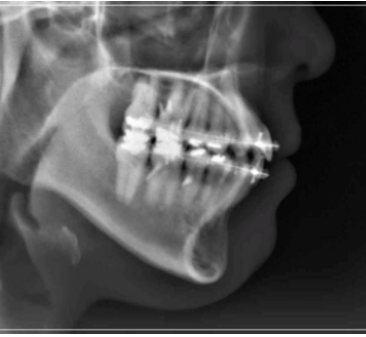

성장 중의 부정적인 문제로 인해

발생한 개방교합은 보통 치아를

교정하면 위와 같은 불편함이 해결 될

것이라고 생각하시는 분들이 많은데,

만일 이러한 개방교합이 턱관절 질환에

의해 발생하였을 경우 잘 모르고

치아 교정부터 진행하게 되면

턱이 불안정한 상태에서 무리하게

치아를 이동시키게 되기 때문에

오히려 질환을 악화시키거나

개방교합이 다시 재발하는 등 문제가

발생할 수 있어 주의가 필요했어요.